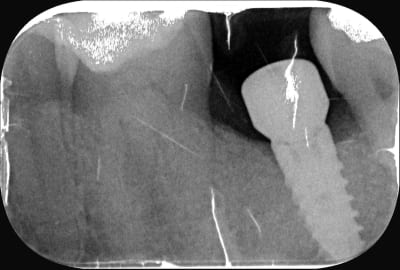

mis seven

https://www.spotimplant.com/fr/implants-dentaire/mis/seven-2

par contre de ce que je vois à la radio c'est pas dévissé....mais plutôt pilier cassé, tu as l'hexagone qui est dans le col et le reste du pilier au dessus....

De mémoire c’est pas à friction comme zimmer….à moins que ça soit un pilier zimmer vissé dedans vu que c’est la même connexion….(tout est envisageable)

A ta place je prévois l’outil zimmer de retrait de pilier….et un petit tourne à gauche pour sortir l’hexagone cassé sinon tu vas galèrer….

Encore un grand merci Pluton, dépose facile et hexagone effectivement fracturé, boulonné sur la vis, il est venu avec la prothèse sans nous embêter.

la base: une radio rétroalvéolaire bien contrastée et bien orthogonale à l'implant pour qu'il y ait le moins de déformations et donc qu'on puisse répertorier toutes les caractéristiques

ensuite mes 2 sites de référence: osseosource et spotimplant

et il suffit de suivre les menus déroulants: type d'implant, forme, type de spires, microspire au col, caractéristiques de l'apex, de la connexion, etc....

et donc çà va te donner une liste de correspondances.....et là c'est l'expérience et les connaissances (le fait de connaître, avoir vu, manipulé...) qui font la différence...